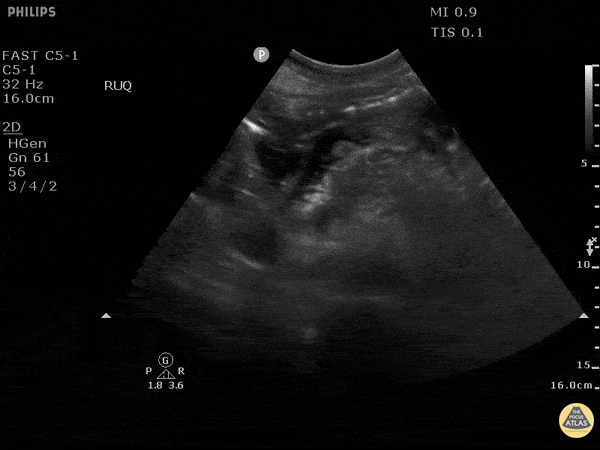

In this case an elderly patient presented with severe back pain and an ultrasound exam was performed to evaluate the aorta. Instead in this transverse view, the pancreas was identified which appears enlarged with surrounding fluid. Besides appearing enlarged, an important finding in this scan is the hypoechoic regions which are indicative of necrosis. Image courtesy of Robert Jones DO, FACEP @RJonesSonoEM Director, Emergency Ultrasound; MetroHealth Medical Center; Professor, Case Western Reserve Medical School, Cleveland, OH View his original post here